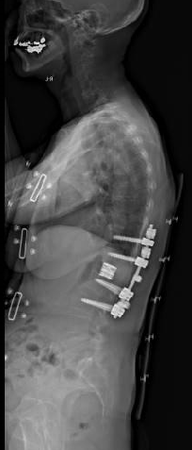

典型的な思春期特発性側弯症遺残変形・進行に伴う変性後側弯症・成人脊柱変形の患者さんです。正面・側面のバランスは破綻していて、難治性腰痛・脊柱管狭窄由来の下肢神経痛のためほぼ寝たきりとなっていました。

通常通り侵襲を軽減する目的で腰椎側方経路椎体間固定術、後方矯正固定術を2回に分けて行いました。正面・側面のバランスは良好で生理的な腰仙椎・体幹のshapeが獲得されています。腰痛、下肢神経痛は皆無となり、適度の散歩など穏やかな日常生活がおくれるようになりました。